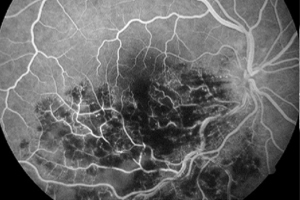

Fluoreszeinangiographie der Netzhaut

Unter einer Angiografie versteht man eine Gefäßdarstellung, mit der die Durchblutungssituation der Netzhaut beurteilt werden kann. Dies ist unter anderem wichtig bei altersabhängiger Makuladegeneration, diabetischen Netzhautveränderungen oder Durchblutungsstörungen z.B. aufgrund einer Thrombose, oder auch Tumoren.

Um die Gefäßdarstellung durchführen zu können, wird ein gelber Farbstoff in die Armvene injiziert. Anschließend werden mit einer speziellen Fotokamera Bilder von den Blutgefäßen am Augenhintergrund angefertigt. Aufgrund des in die Blutbahn gelangten Farbstoffes können die Gefäße, Gefäßverschlüsse, Gefäßneubildungen (Neovaskularisationen) und auch durchlässige Bereiche (Leckagen) gut dargestellt werden. Die fotografischen Aufnahmen ermöglichen eine genaue Darstellung der abnormen Blutgefäße oder der Größe und Lage des Gefäßverschlusses.

Die Fluoreszeinangiographie wird ambulant im Rahmen einer speziellen Sprechstunde durchgeführt.

Normalbefund

Venenastverschluss